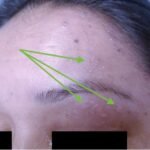

A 36-year-old immunocompetent female presented to the emergency department (ED) with five days of headache and left-sided facial pain. Physical exam showed conjunctival injection of the left eye with multiple vesicular lesions distributed along the V1 dermatome. Labs were remarkable for mild elevation in erythrocyte sedimentation rate (ESR) and c-reactive protein (CRP) with no elevation in white blood cell (WBC) count. Computed tomography (CT) with contrast of the neck revealed soft tissue stranding around the parotid gland. The patient was diagnosed with herpes zoster ophthalmicus (HZO) with concurrent ipsilateral parotitis and subsequently treated with valacyclovir, ofloxacin eye drops, topical erythromycin ointment and amoxicillin/clavulanic acid. Upon follow-up ten days after discharge, the patient noted marked improvement in her symptoms and reduction in pain. To our knowledge, this is the first case described in medical literature of a female patient with HZO and ipsilateral parotitis.